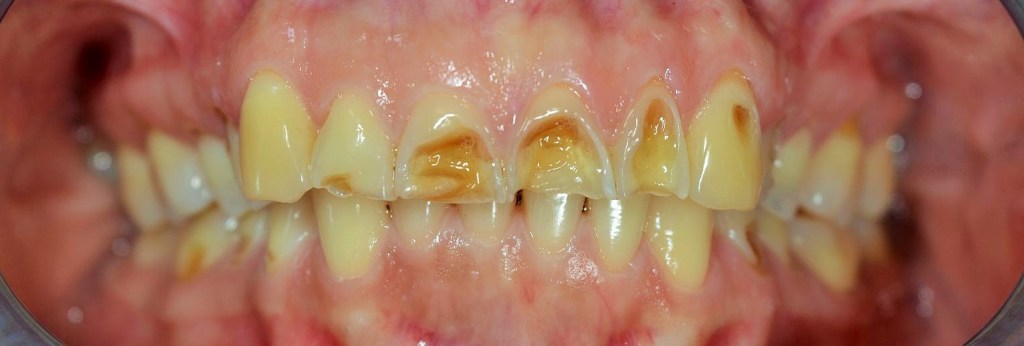

Kozmetikai és funkcionális kezelés: a kopott, elszuvasodott fogak szanálásával, hiányzó frontfogak híddal történő pótlásával, harapás megemelésével.

A választott korona típusa: CAD/CAM (komputer vezérelt tervezés/megmunkálás) technológiával készült cirkónium (fémmentes) szóló koronák, front híd.

A választott fogszín: BL 3 .

A protetikai munka elkészülésének ideje: 10 munkanap.